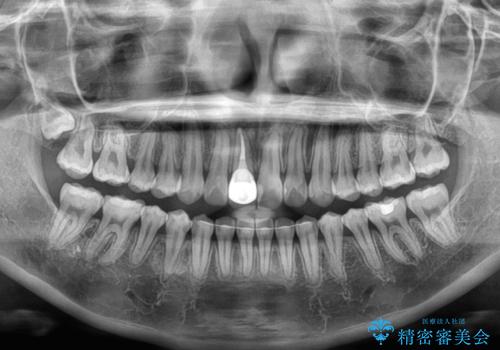

舌の突出癖による開咬と前歯の突出 インビザライン矯正治療

矯正治療の途中で前歯の根管治療とオールセラミッククラウンによる補綴治療を行い、その後インビザライン1セットを用いて細かい部分を仕上げました。